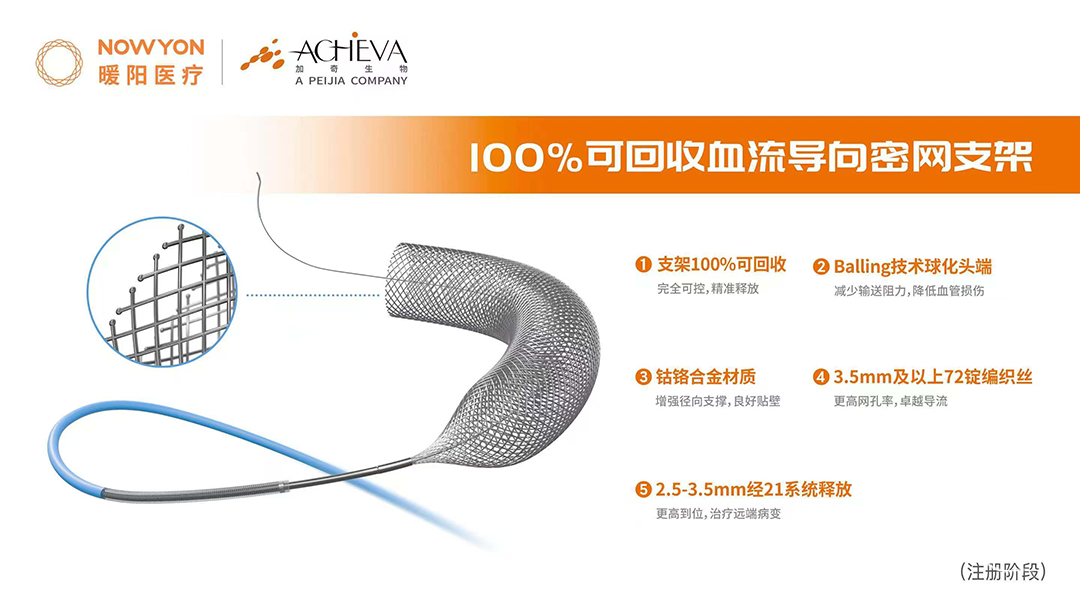

· YonFlow®血流导向密网支架 4.5*45mm

YonFlow®血流导向密网支架头端打开顺利;通过“推拉结合”的方式打开YonFlow®后半段。

造影提示YonFlow®血流导向密网支架头端和后半段打开良好。

YonFlow®血流导向密网支架释放结束后,支架导管回超到支架头端,行支架内微导丝按摩。

蒙片提示支架展开良好。

术后半年复查造影:YonFlow®血流导向密网支架贴壁良好,载流动脉前向血流良好。

V4段夹层动脉瘤伴瘤腔内血栓形成,瘤体较大,密网支架可有效降低手术难度和术后复发率。

支架头端锚定位置尽量不要覆盖基底动脉近端,术中支架头端打开顺利,锚定血管壁牢靠,未出现支架头端下移和前移的情况。

由于瘤颈处稍狭窄,支架通过后影响后半段支架的打开,通过“推拉结合” 的方式顺利将后半段支架打开,提示支架优秀的展开能力。

本例手术应用可100%回收的血流导向密网支架——YonFlow®血流导向密网支架,手术操作顺利,术中支架远端“Balling技术球头设计”带来了输送顺畅且远端安全。术中独创的可回收功能可实现支架从微导管100%释放后仍能回收至微导管,同时输送系统支架近端/远端还带有定位Mark点,能帮助医生在术中重新释放和精确定位,反复调整支架释放位置直至最合适处,从而进一步提升手术精准度和效果,增加手术的成功率和安全性,支架最终打开后贴壁良好。